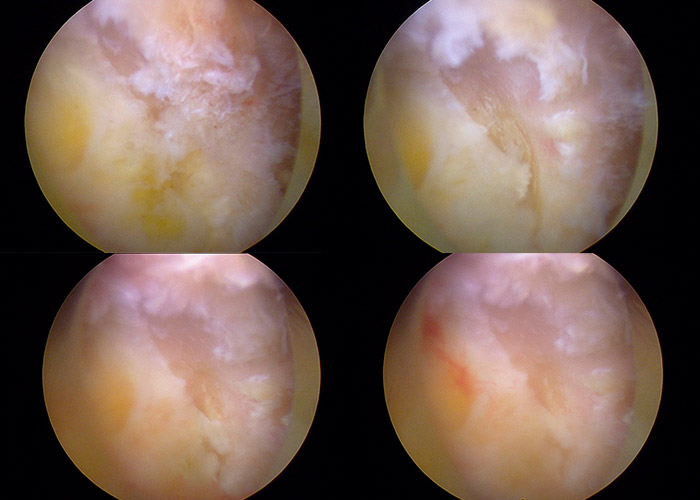

Primero se procede a la identificación del ligamento amarillo y a la identificación de la lámina superior e inferior que limitan la ventana interlaminar.

Se procede a realizar una laminectomía parcial en la lámina superior hasta identificarse la punta de la fase descendente. Se comprueba su adecuada liberación de las estructuras neurológicas en el lado derecho.

Posteriormente se procede a la identificación de la compresión en el canal medular. Se comienza la retirada del ligamento amarillo de la región central para descomprimir las estructuras neurológicas.

Se procede al acceso al lado contra lateral, mediante el mismo portal posterior derecho, para liberar las estructuras neurológicas del lado izquierdo y comprobar la adecuada liberación y descompresión.